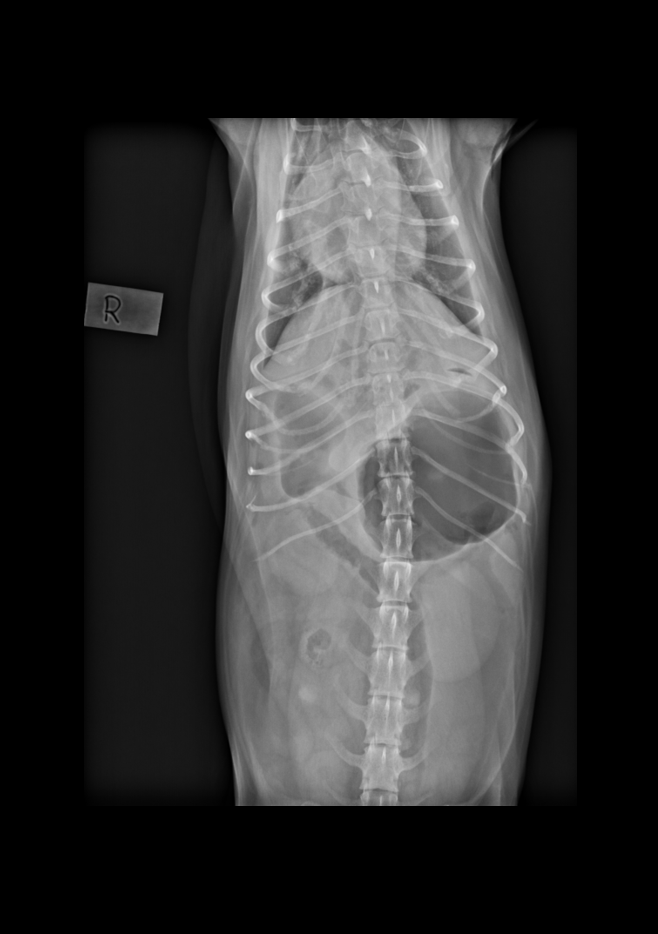

Signalement: Portugisisk vannhund, tispe, 2 år. Anamnese: Oppkast i 2 dager, stort sett uproduktive brekninger siste døgnet. Ingen matlyst eller avføring i disse dagene. Hadde mageproblemer for 2 uker siden, trolig fått i seg pinnekjøtt da. Nedstemt ved ankomst klinikk. Ingen informasjon om siste løpetid.